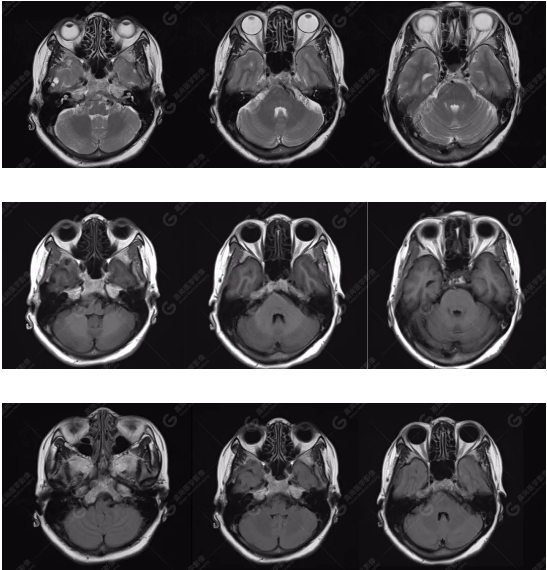

檢查圖像

雙側(cè)大腦半球?qū)ΨQ,灰白質(zhì)對(duì)比正常,右側(cè)顳部見一囊狀長T1長T2信號(hào)影,F(xiàn)LAIR序列呈低信號(hào);余腦實(shí)質(zhì)內(nèi)未見局灶性信號(hào)異常。各腦室、腦池大小、形態(tài)均正常,中線結(jié)構(gòu)居中,幕下小腦、腦干無異常。矢狀面示垂體大小形態(tài)正常,未見局灶性信號(hào)異常。